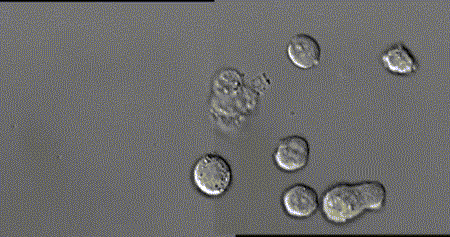

中性粒细胞可以吞噬和消化有害病原体,图中为中性粒细胞追击金黄色葡萄球菌的过程。